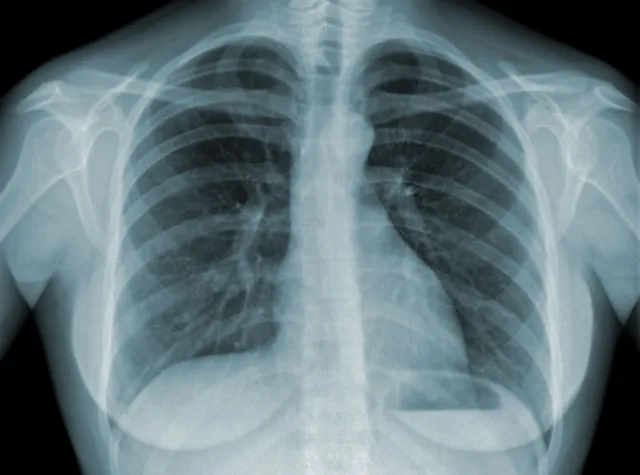

Sztuczna inteligencja z 90-procentowym prawdopodobieństwem określa, kto umrze z powodu infekcji SARS-CoV2, jeśli już się zarazi - oraz przewiduje, kto będzie potrzebował respiratora. Według naukowców wyniki te powinno się uwzględniać w ustalaniu kolejki szczepień.

Wykorzystując dane medyczne prawie 4 tys. duńskich pacjentów z COVID-19 naukowcy z Uniwersytetu Kopenhaskiego nauczyli system sztucznej inteligencji określania ryzyka ciężkiego przebiegu i śmierci z powodu infekcji odpowiedzialnym za pandemię wywołaną przez koronawirusa.

W przypadku osób, które nawet jeszcze się nie zakaziły, program potrafi z 90 proc. pewnością oszacować ryzyko zgonu, gdyby do infekcji faktycznie doszło. Po przyjęciu pacjenta do szpitala potrafi też z 80 proc. dokładnością przewidzieć, kto będzie potrzebował respiratora.

Program wskazał na szereg czynników zwiększających ryzyko zgonu i ciężkiego przebiegu choroby. W kolejności od najważniejszego są to: wskaźnik masy ciała (BMI), wiek, wysokie ciśnienie krwi, płeć męska, choroby neurologiczne, chroniczna obturacyjna choroba płuc, astma, cukrzyca, choroby serca.